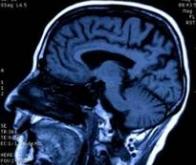

La première étude a porté sur 128 personnes venant du Royaume-Uni, des Etats-Unis et d'Australie, toutes prédisposées à développer la maladie d'Alzheimer à un âge précoce. Elle montre que les premières modifications provoquées par la maladie d'Alzheimer apparaissent chez les sujets génétiquement prédestinés vingt-cinq ans avant les premiers troubles de la mémoire et les altérations cognitives. Cette étude montre également que la hausse des niveaux de béta-amyloïdes dans le liquide céphalo-rachidien est l'événement qui survient en premier. Ces protéines, qui siègent entre les cellules du cerveau, sont une des causes principales de la maladie d'Alzheimer.

D'autres changements apparaissent quinze ans avant ces troubles : les protéines béta-amyloïdes deviennent visibles sur un scanner du cerveau, les niveaux de protéine tau, qui entraînent une dégénérescence neurofibrillaire, augmentent dans le liquide céphalo-rachidien, et enfin, certaines zones du cerveau rétrécissent. Une réduction de l'utilisation du glucose par le cerveau et des problèmes de mémoire légers peuvent être détectés, eux, dix ans avant l'arrivée des symptômes complets.